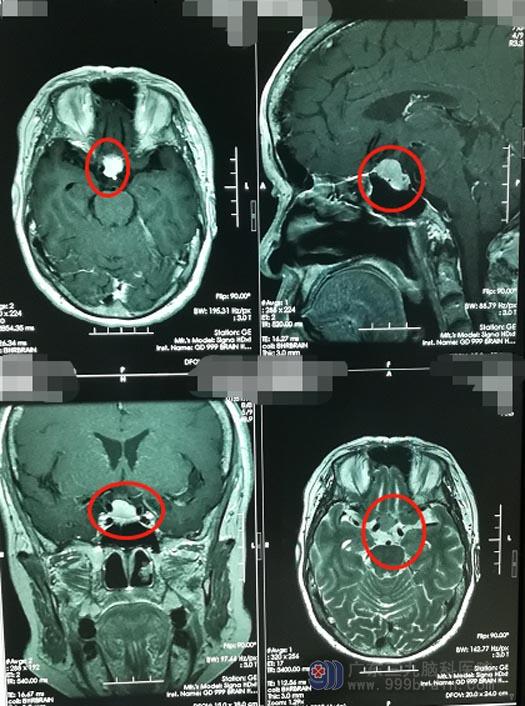

在热心同乡的介绍下,钟阿姨住进了广东三九脑科医院神经外五科。主管医生毕中胜安排她进行了相关的检查。MRI结果显示:鞍结节占位性病变,大小约12mm×13mm,考虑脑膜瘤可能性大。

鞍结节脑膜瘤多发生在成人,有78%的患者会出现轻微头痛,以双颞部最多。钟阿姨肿瘤所在的位置,如果继续增大会压迫到神经,出现尿崩,视力、视野障碍,甚至失明等症状。目前最主要的治疗方式,是通过外科手术进行肿瘤切除,在早期就进行手术,也可以减少鞍结节脑膜瘤不断沿骨缝生长造成的残留。

因为鞍结节脑膜瘤是处在脑子的正中央,手术难度相对较大,医院副院长、神经外五科主任鲁明带领团队为钟阿姨选择了全麻下行内镜“经鼻蝶鞍结节脑膜瘤切除术”,手术过程中保护好垂体功能,将肿瘤顺利全切。